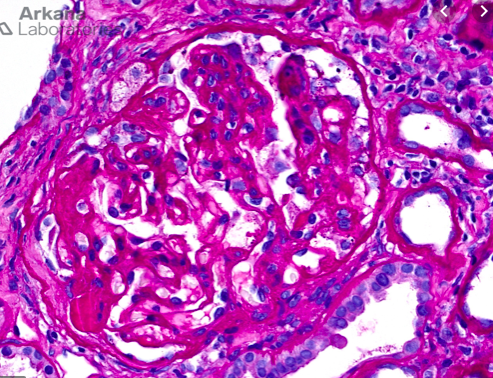

IgA DEPOSIT IN MESANGIUM AND CAPILLARY WHICH ACTIVATES IgG AND CAUSES DESTRUCTION AS MESANGIAL PROLIFERATION AND MATRIX PROLIFERATION